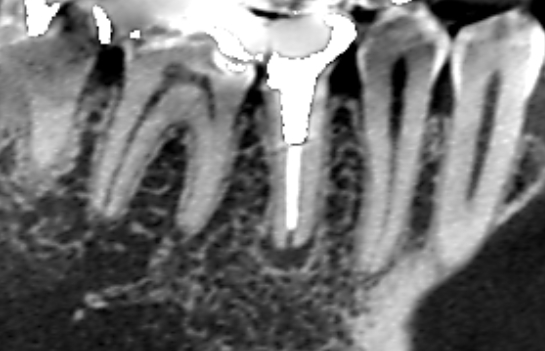

続きを読むVol.11 専門によって治療方針が変わる。再根管治療で抜歯せずに済んだケース。

- マイクロスコープ歯科・ 再根管治療・ 抜歯回避・ 歯科症例・ 精密根管治療

右下の奥歯が痛くなり、右下の第一大臼歯と第二大臼歯に膿が見つかり口腔外科で2本の抜歯をすすめられた患…